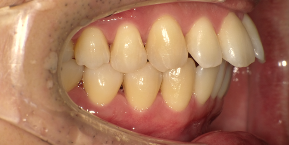

33歳女性のビフォーアフター

| 診断 | 空隙 |

| 治療方針 | 治療方針:前歯の咬合関係改善と空隙閉鎖を主な目的にて主にIPR(歯と歯の間をわずかに削合してスペースを獲得する方法)を組み込んだ動的矯正治療を行い、空隙、前歯咬合を改善後、保定を行う。臼歯部の咬合関係はプランの都合上維持することとした。 |

| 治療費 ※ | 67万8千円(診断、型取り、矯正中のメンテナンス、保定装置を含む料金) |

| 治療期間 | 6か月 |

| リスク | 1日20時間以上マウスピースを使用できない場合、歯が動かなかったり、想定しない誤差により不完全に終わる可能性がある。装着時や食事時に痛みを伴う。歯肉退縮や虫歯になるおそれがある。また、指導通りに装着できていない場合や適切なブラッシングが出来ていないとそのリスクが高くなる。歯根が短くなることがある。ごくまれに歯の神経が損傷してしまうことがある。過去にぶつけたり深い虫歯治療をしたことがあるとそのリスクはやや高くなる。矯正後には保定装置が必要。適切な使用ができない場合、後戻りの原因となる。将来的に歯並びが動いて再矯正が必要な場合がある。親知らずが正常に生えていない場合、その可能性がやや高くなる。 |

※ 治療費は、治療当時の費用で、現在の費用と異なる可能性があります。現在の費用は治療費のページでご確認くださいませ。